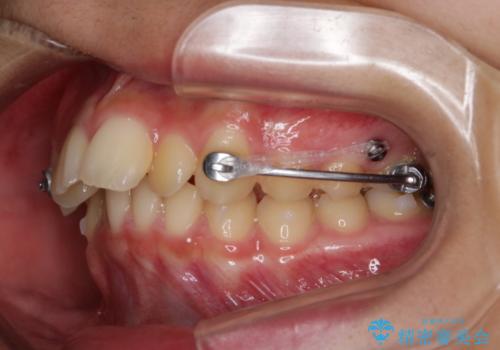

非抜歯で劇的に出っ歯を改善!インビザラインとカリエールの組み合わせ治療

- インビザライン カリエール

- 患者様、出っ歯のお悩みで来院されました。

骨格の分析を行ったところ上顎も出てはいるのですが、下顎が引っ込んでいる状態であるということがわかりました。

よって上顎の歯を抜いて治療をするのではなく、カリエールという器具を使用して下顎を前に引っ張り出しながら上顎を引っ込めるという治療を行うことにしました。